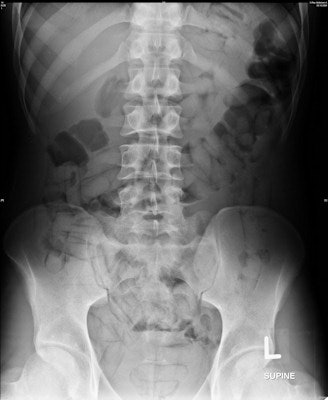

The generally accepted radiological exam is a plain abdominal radiograph in the supine position. However, the detection rate for drug-filled packets is highly variable in the literature, and sensitivities ranging from 58.3% to 90% have been reported. Thus, plain abdominal radiography is considered a flawed screening method for identifying drug mules.

In all confirmed drug carriers, the "double-condom" and "halo" signs (100%) were detected by each radiologist, Rashid and colleagues found.

"These radiological signs occur due to inevitable air inclusion during manufacturing of drug packets, which creates the specific double-condom sign if the pack is projected longitudinally or the halo sign if it is imaged transversely," they wrote. "However, the 'rosette' sign (due to trapped air at the twisted end of a pack) is not easy detectable on plain radiograph and was only reported in a single (6.25%) case by one radiologist in the experienced group."

Other signs include the "tic-tac" and "parallelism" signs, which are created by the parallel arrangement of longitudinal packs within the large bowel (seen in three cases). Suspicious gas formation in the rectum was reported in two cases by one radiologist in the inexperienced group, but these cases were confirmed to be negative.

In terms of shape, nearly all the drug mules (93.75%) ingested typically shaped longitudinal or tubular body packs wrapped in plastic or condoms. The longitudinal or tubular shape was observed in each case (100%) on imaging, whereas the round shape was observed in one (6.25%) case by all radiologists.

In terms of size, the average length of the longitudinal packs was 4.93 cm (range, 2.5-6.8 cm; median, 5.0 cm) and the width was 2.12 cm (range, 1.4-3.1 cm; median, 2.1 cm). The round drug packs measured 2.0 cm to 5.6 cm in diameter, with an average diameter of 3.18 cm (median, 2.5 cm). The shapes and size measurements on DR were correct according to the measured packs in the feces.